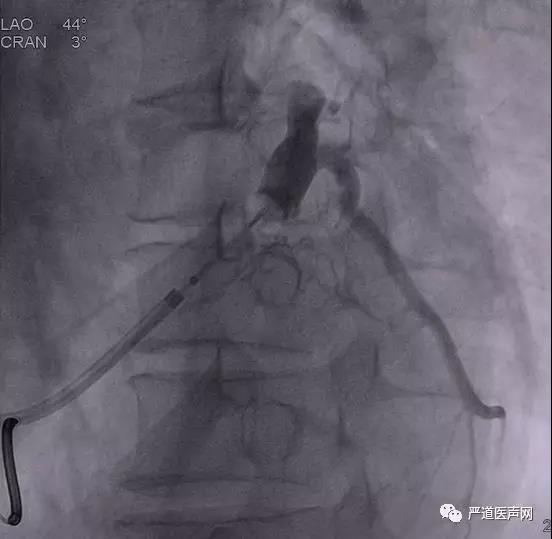

术中使用造影球囊显示冠状静脉分支,选择粗大侧静脉为靶静脉。

选择Sprial L导线,通过PTCA导丝将导线送入侧静脉远端,贴靠稳定。

沈院长术后针对该病例做了如下解读:患者术中影像提示靶静脉开口有成角,故选择超滑导丝。E1-E4均无膈神经刺激,阈值:E1=1.7V@0.4ms,E2=1.0V@0.4ms,E3=0.9V@0.4ms,E4=2.5v@0.4ms。E4阈值较高,考虑该部位血管较粗,电极无法紧密贴靠有关。患者术后QRS波时限达到120ms,经优化参数后,患者QRS波宽度从术前的190ms缩短到术后120ms,预期对患者心功能有明显改善。